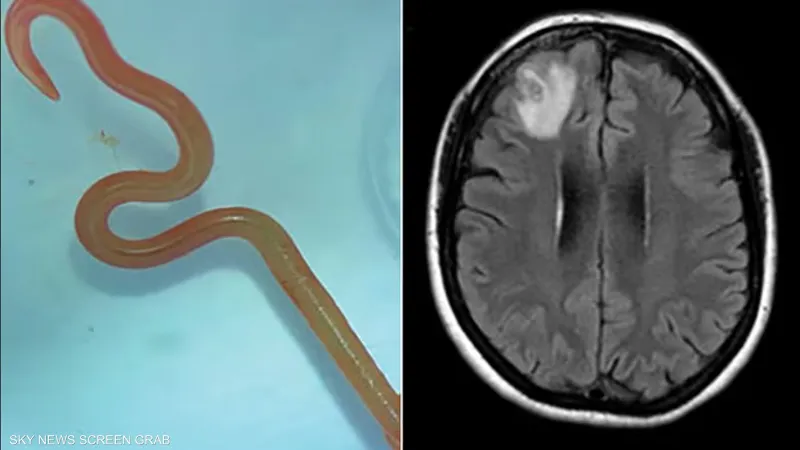

وبحسب وسائل الإعلام، تم نقل المريضة، وهي من جنوب شرق نيو ساوث ويلز، إلى مستشفى كانبرا بعد عام من الشكاوى المتزايدة من الاكتئاب وفقدان الذاكرة، بالإضافة إلى مجموعة من الأعراض الجسدية.

وبينت فحوصات الأشعة المغناطيسية وجود شذوذات في دماغها؛ ما استدعى إجراء عملية جراحية.

وسبب هذا الاكتشاف جدلًا واسعًا بين الأطباء والعلماء، خاصة بعد تحديد نوع الدودة الدائرية باسم “Ophidascaris robertsi”، وهي نوع معروف بأنه يصيب الثعابين بشكل أساسي. هذه الحالة تعتبر الأولى من نوعها عالميًّا فيما يتعلق بإصابة البشر بهذا النوع من الطفيليات.

ونظرًا لعدم وجود معلومات سابقة عن كيفية معالجة هذا النوع من الطفيليات في البشر، فإن الفريق الطبي بقيادة الدكتور سيناناياك قام بتطبيق مجموعة من التدابير الاحترازية، بما في ذلك استخدام الأدوية التي لا تسبب التهابات خطيرة عند موت الطفيلي.

وتظهِر هذا الحالة النادرة المتزايدة للأمراض الناجمة عن الحيوانات، حيث يُرجِح أن تكون المرأة قد أصيبت بالطفيلي عن طريق تجميع الأعشاب البرية بالقرب من بحيرة يُعرف بأنها موطن للثعابين.